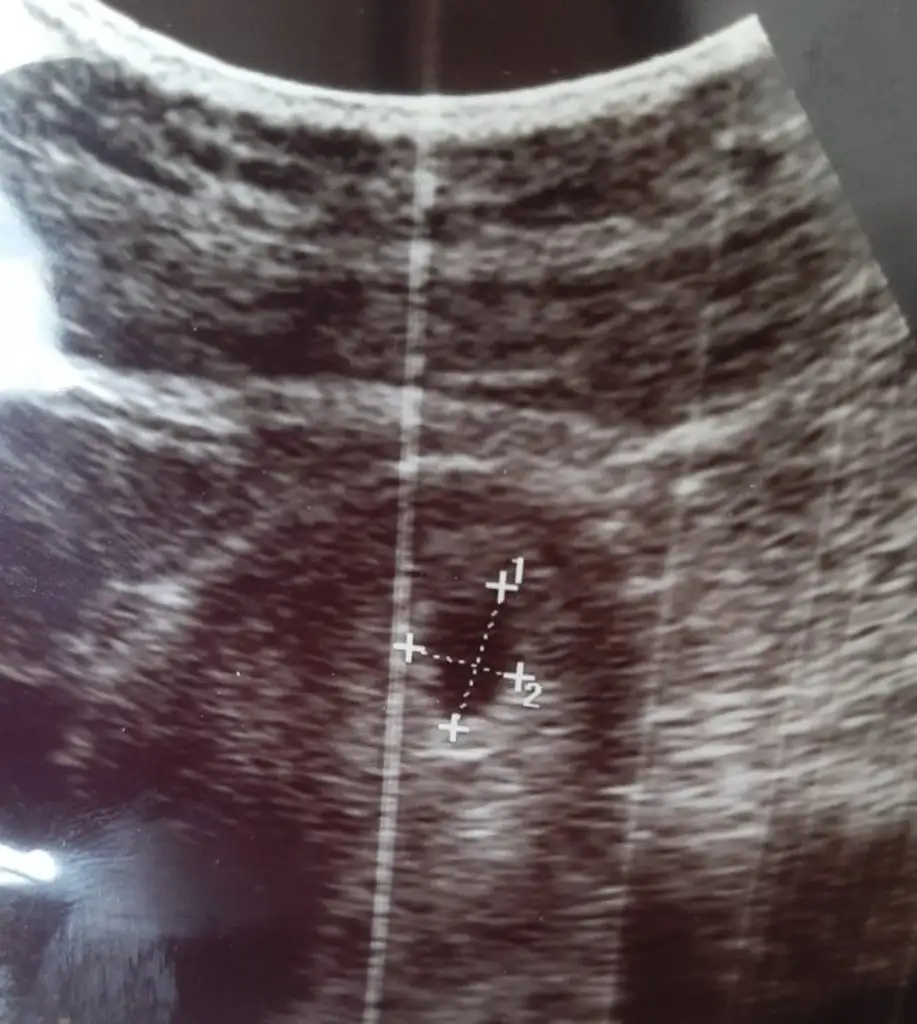

Benide.yorumlarmisinizzzz 12+6 renkli olanda diğerleri siyah olanlar 11+5 haftalıkBence kiz

Kız gibi ama doktor tahmin yapmadı mı hiç ben anlamam sadece fikir yürüttüm

Kıza benzetildiKız gibi ama doktor tahmin yapmadı mı hiç ben anlamam sadece fikir yürüttüm

TeşekkürlerKonu sahibininki kız, sizinki de erkek bence

Nub teorisine göremi yorumladınız acaba ya da hissiyat mıKonu sahibininki kız, sizinki de erkek bence

Bana da yorum yaparmisinKonu sahibininki kız, sizinki de erkek bence

Görüntüsü çok kıza benziyor bende anlamıyorum nubu fazla heralde ürüme organı 30 cm büyükse erkek diyorlar küçükse kızKıza benzetildiNub teorisini hiç bilmiyorum sormak istedim